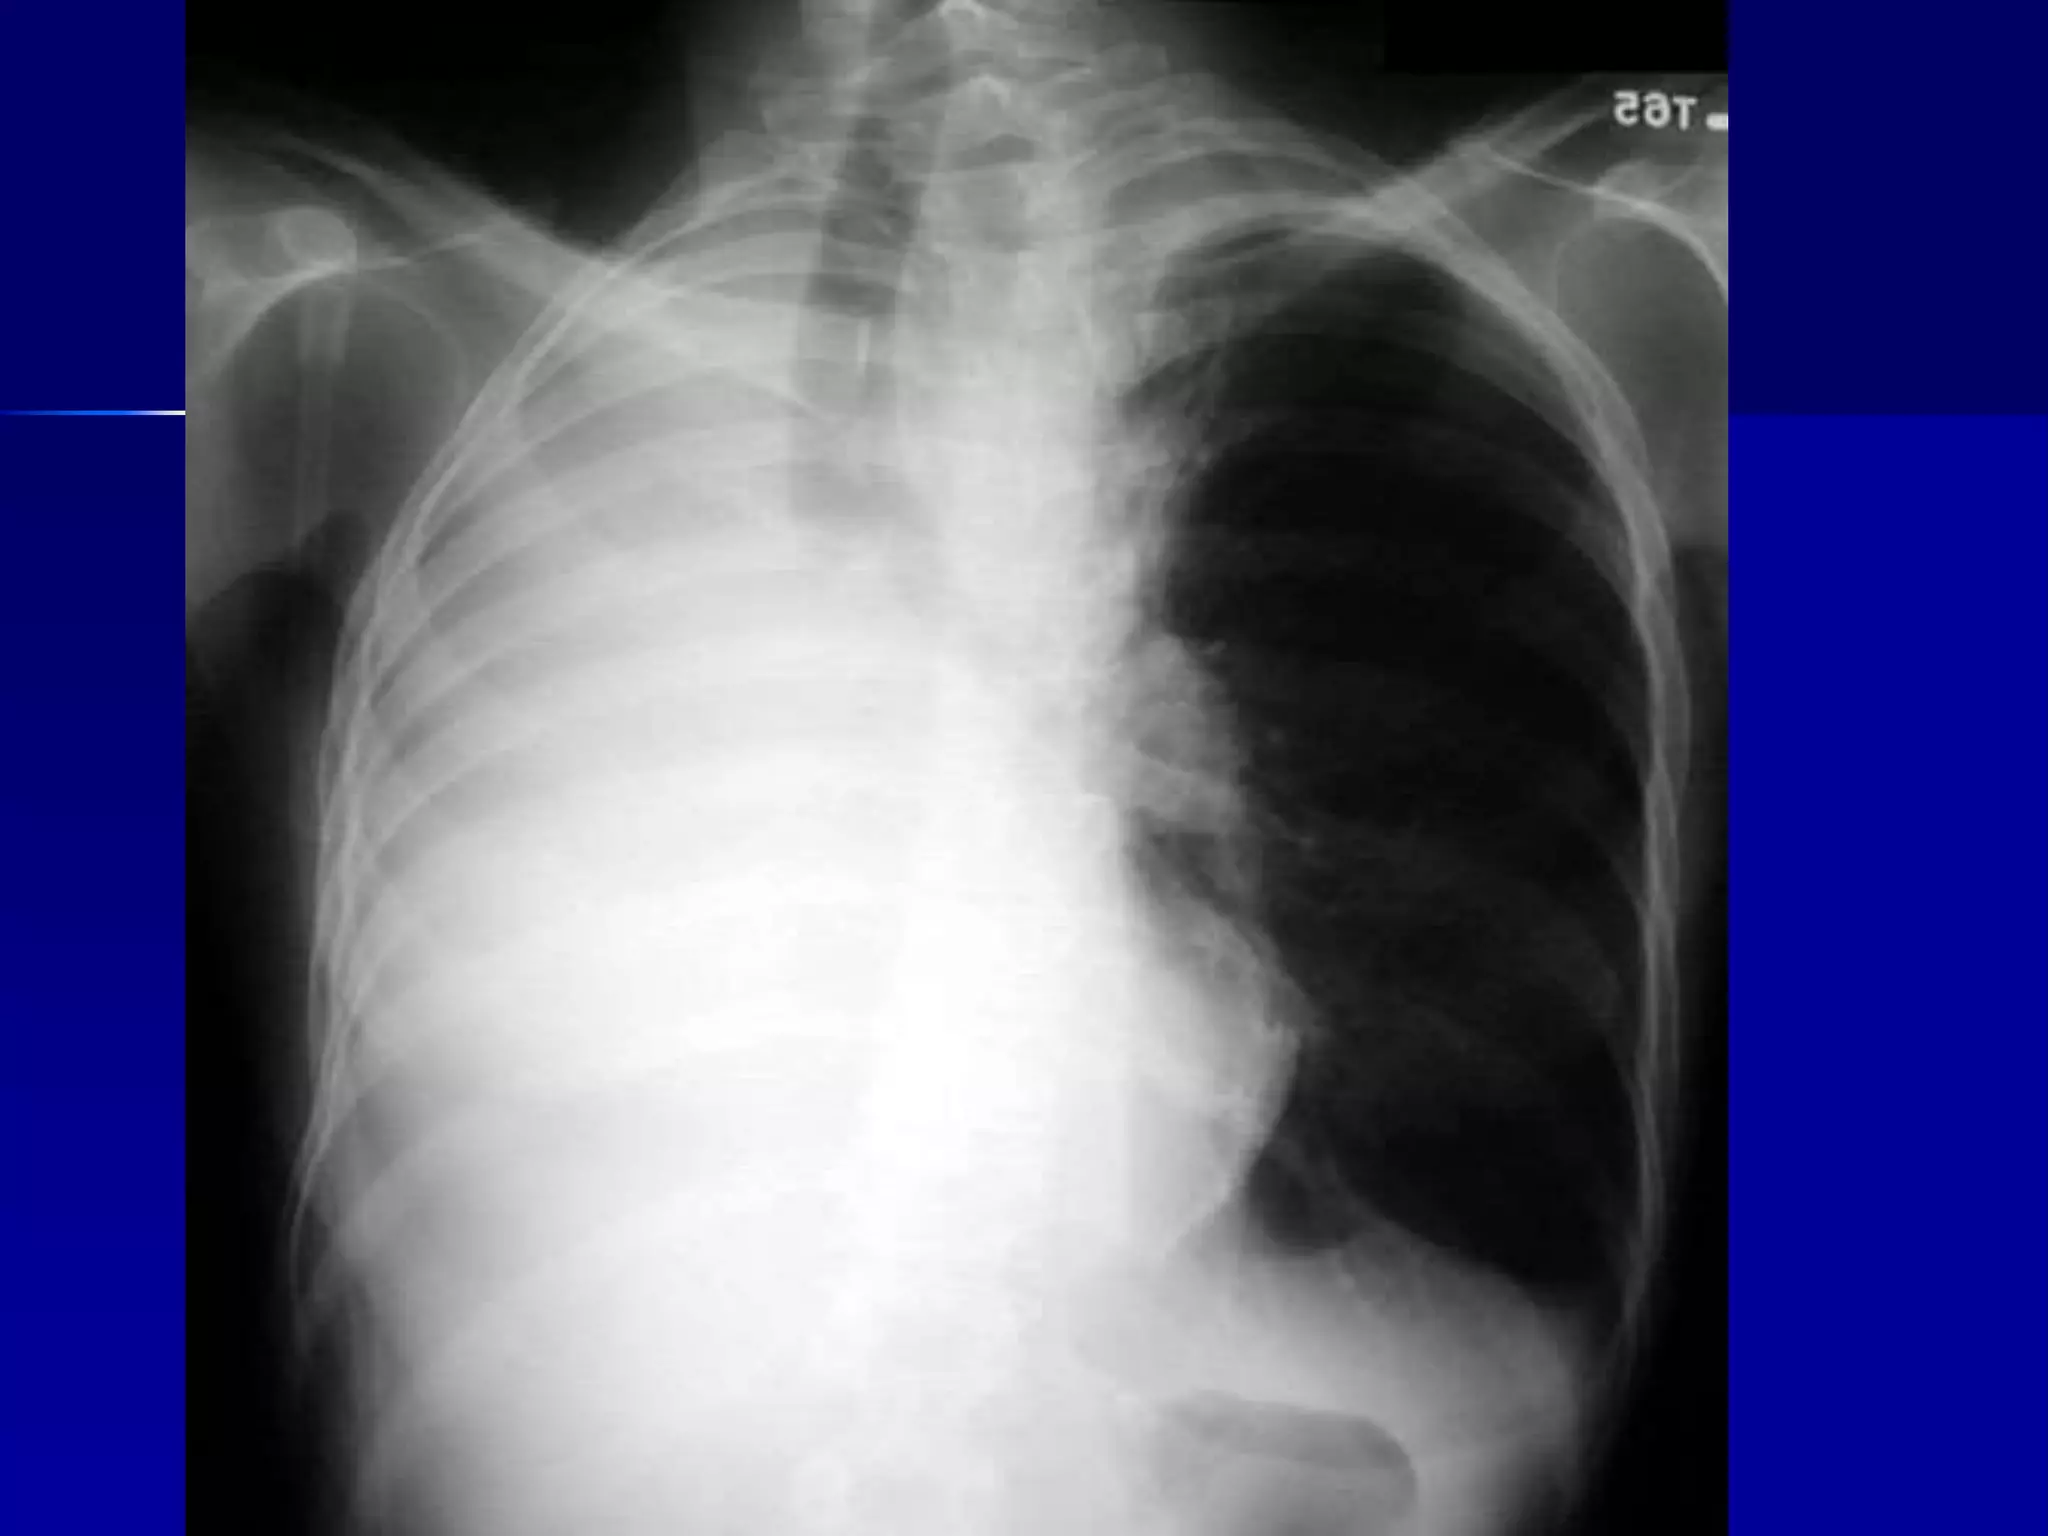

Atelectasis Right Lung

 Homogenous density right hemithorax

 Mediastinal shift to right

 Right heart and diaphragmatic

silhouette are not identifiable

 Atelectasis Right Lung

 Open Bronchus Sign

 Right heart and diaphragmatic silhouette

are not identifiable